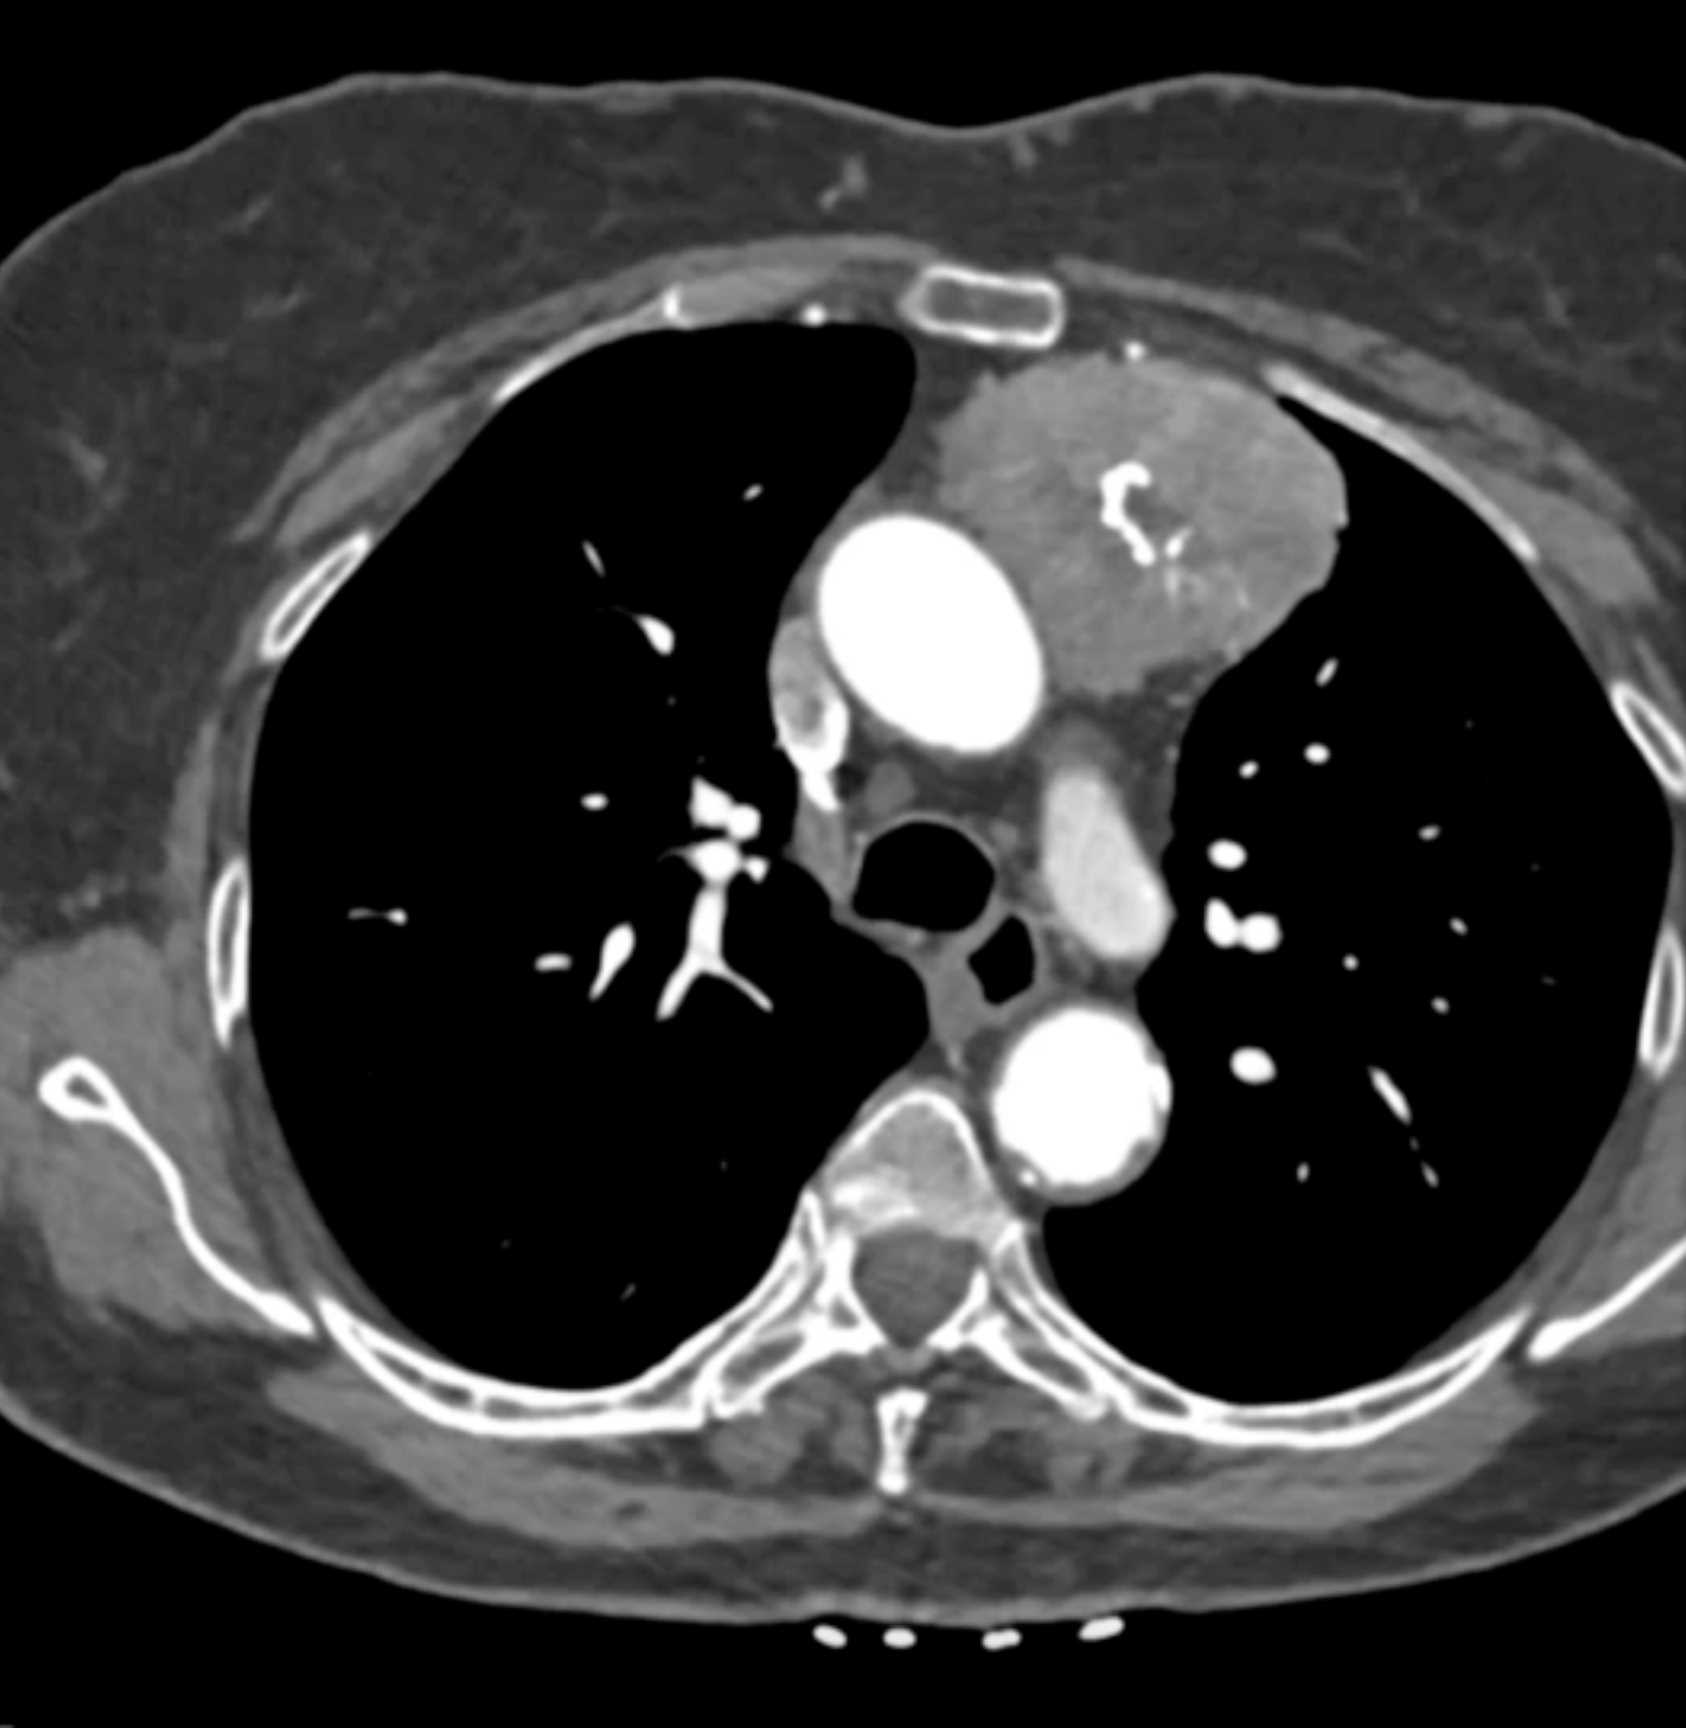

Thymic Carcinoma